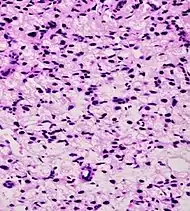

| Small-cell carcinoma | 0.3–2%[14][15][notes 1] | ![]() |

Half of cases have usual acinar components[1] |